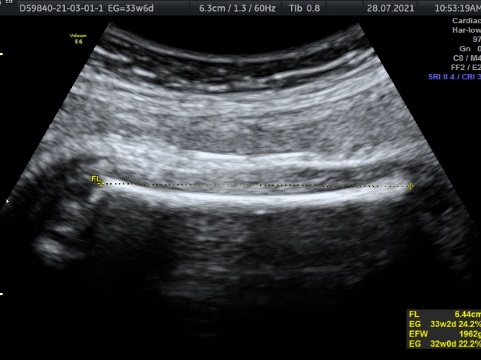

En cualquier semana de embarazo. Es un estudio que nos habla de la oxigenación que esta teniendo tu bebé a través de diferentes flujos sanguíneos ( cordón umbilical, cerebero, arterias uterinas, flujos del corazón. Es un estudio que se realiza para verificar Bienestar Fetal. Tiene una duración de 1 hora y al finalizar el estudio , se realiza 3D, 4D, 5D. Costo $1600